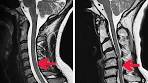

Lahmung durch bandscheibenvorfall

Peroneusl hmung